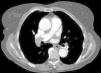

Para além da avaliação da carga embólica na TCMD, foram efetuadas medições quantitativas dos diâmetros das estruturas vasculares (VCS e VA) e cardíacas (VD, VE, ratio VD/VE; SC, AP, Ao, ratio Ap/Ao) relacionadas com a árvore pulmonar. O desvio do SIV e o refluxo de contraste na veia cava inferior (VCI) foram avaliados qualitativamente, de forma a definir os sinais de DVD (Figuras 2-5).

Na angio-TC, o grupo B apresentou diâmetros do VD, ratio VD/VE (p-0,002), VCS, VA e SC superiores. Os diâmetros da AP e o ratio AP/aorta foram semelhantes.

Na angio-TC, o QS correlacionou-se linearmente com os parâmetros de DVD avaliados (diâmetros do VD, VCS, VA e SC; ratio VD/VE e AP/Ao; percentagem de sobrecarga no SIV e de refluxo na VCI), conferindo à carga embólica avaliada por QS um potencial multiparâmetros que ainda não se encontrava descrito na literatura.